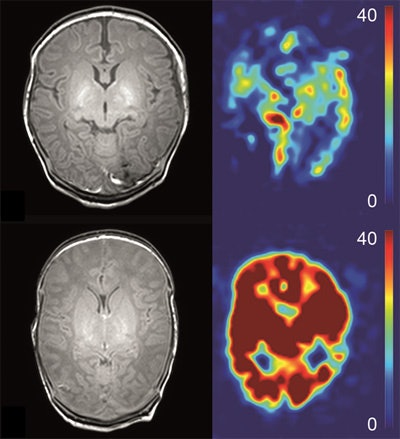

Cranial ultrasound and MRI -- conventional, diffusion-weighted imaging (DWI), DTI, magnetization transfer imaging (MTI), MR spectroscopy, and ASL perfusion -- are being used to image neonates with HIE. ASL perfusion MRI, a technique that inverts arterial blood water flowing toward the brain and serves as a tracer to evaluate brain perfusion, has been used with adults for more than 20 years. However, due to technical hurdles that only recently have been resolved, it has not been used to image newborns and infants, explained Dr. Jeroen Hendrikse of the department of radiology at University Medical Center Utrecht. He is head of a team investigating the use of noninvasive ASL MRI in neonates to visualize and quantify brain perfusion in mL/min/100gr brain tissue.

"With most MRI exams that are performed, structural damage can be assessed, and the infarction can be seen, but no perfusion parameter has been available. ASL provides a relatively simple noninvasive method to obtain hemodynamic (perfusion) information from a scan that takes approximately five minutes," he said. "In a study of 28 neonates imaged four days after birth published in the January 2015 issue of European Radiology, ASL not only complemented known MRI parameters in the prediction of outcome, but also provided additional unique and valuable information. Perfusion adds additional prognostic information, which was a gratifying surprise to us."

The study determined that basal ganglia and thalami perfusion (deep gray matter) was higher a few days after birth in neonates followed for up to 18 months who had adverse outcomes of cerebral palsy or death. "We think that in conjunction with MR spectroscopy, it can be used as an outcome biomarker, as ASL perfusion had positive and negative predictive values of 100% and 96% respectively. It allows for an evaluation of the reperfusion phenomenon, which is related to delayed cell death. We also think that ASL may be useful to evaluate the effectiveness of neuroprotective therapies," he added.